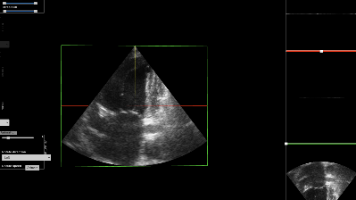

摘要:本文提出利用扩散模型(DDPM)生成高质量心脏超声影像的创新方案。针对医学影像标注数据稀缺且成本高的问题,研究团队通过语义标签图引导的扩散模型,实现了从解剖结构图生成逼真超声影像。相比传统GAN,该方案训练更稳定,且能生成多样化图像。实验表明,完全使用AI生成数据训练的分割模型,在真实测试集上Dice分数提升9.2%-13.9%。该模型还能处理极端异常解剖结构,展现出强大的泛化能力,为罕见病